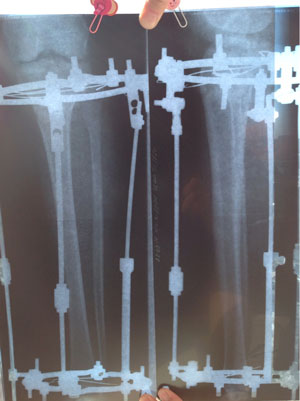

Рентген в 2 месяца.

Сращение идёт отлично, снятие аппаратов в 3 месяца!

Nikol, ножки супер!